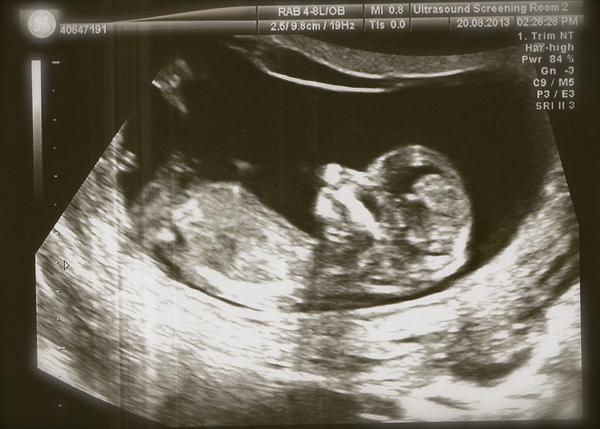

Jinak holky mne je stale zle, obcas zvracim obcas to ustojim, ale porad zaludek na vode 😒 😝 Uz se tesim az to prejde. Dnes jsme byli s mazelem za porodni babou (tady v UK midwife) tak to bylo o nicem, jen mi vzala krev a tlak zmerila a spousta papirovani. 1.screening mame 20.8. takze za 14 dni uz se tesim!! 🙂

@mariiianka Gratulka k UZ 😵 Krásné fotečky 😉 🙂 Tak to vypadá na klučíka??? Však hlavně, že je miminko zdravé 🙂 🙂 🙂 😉 Já bych naštěstí asi měla jsména pro oba, ale to se jednou uvidí...

@barakara Krásná fotečka z UZ 😵 a gratulka k výsledkům 🙂